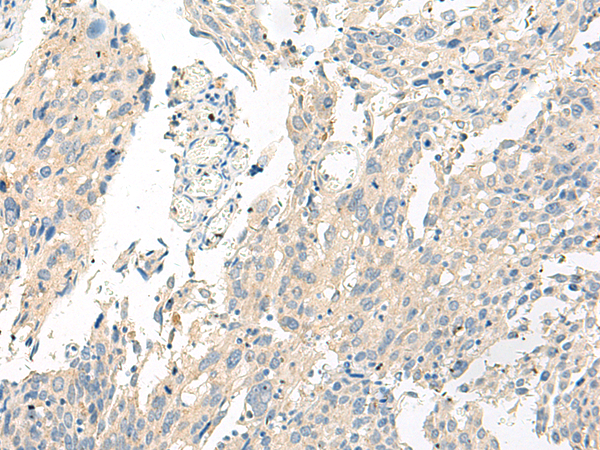

IHC positive control: |

Human cervical cancer and Human breast cancer |